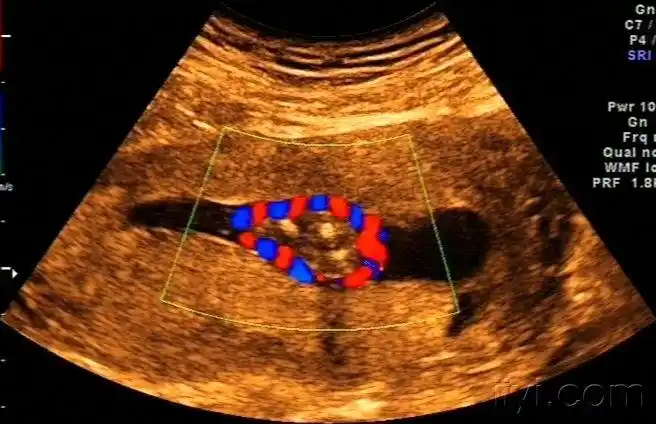

看这个宝宝的脐带绕颈多经典! - 超声医学讨论版 - 爱爱医医学论坛